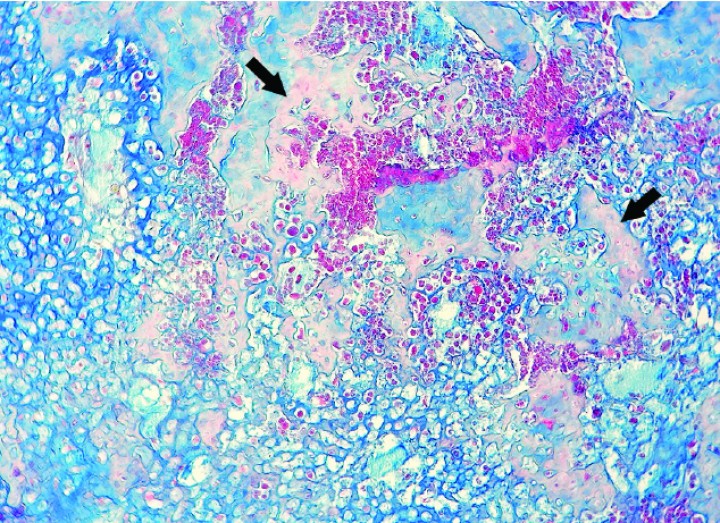

En las 4 cobayas evaluadas con azul alcián, la matriz extracelular se tiñó de color azul intenso con excepción de las zonas osificadas, que eran eosinófilas pálidas a rojas (Figs. 9-12). Las células mostraron un núcleo de redondo a elíptico o irregular con la cromatina laxa o granular, 0-3 nucléolos ocasionalmente prominentes y una cantidad media de citoplasma eosinófilo o basófilo pálido variablemente vacuolizado. La anisocitosis, anisocariosis, pleomorfismo y anaplasia eran generalmente moderados y se distinguían entre 0-3 mitosis por campo de 40 aumentos. En dos cobayas se apreció embolismo de células neoplásicas en vasos sanguíneos y en 3 casos se observaron focos de metástasis pulmonar (Fig. 12). Los niveles de sección evaluados de las múltiples masas de la extremidad posterior hasta zona lumbar de la cobaya 4 no revelaron tejido linfoide, motivo por el cual no se pudo demostrar de forma definitiva que alguna de ellas correspondiera a metástasis en linfonodos regionales. En algunos casos, la neoplasia mostraba amplias áreas de necrosis y/o hemorragia aguda, además de pequeños focos de hemosiderosis.

<p>Cobaya 2. Imagen microscópica de una zona rica en matriz cartilaginosa (azul) de un condrosarcoma con depósito incipiente de osteoide (flechas) en un proceso de osificación endocondral del cartílago neoplásico. (Azul alcián, x220).</p>

Figura 10

Cobaya 2. Imagen microscópica de una zona rica en matriz cartilaginosa (azul) de un condrosarcoma con depósito incipiente de osteoide (flechas) en un proceso de osificación endocondral del cartílago neoplásico. (Azul alcián, x220).